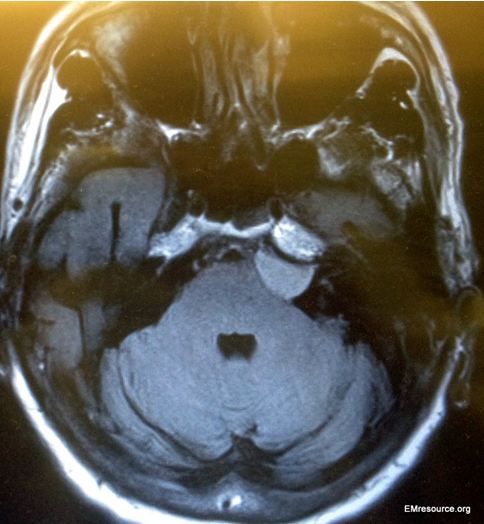

Figure. Brain MRI scan obtained in ED.

A 68-year-old man presents to the emergency department after 4 days of constant and slowly progressive ataxia and possibly some intermittent double vision. He denies vertigo, change in hearing, headache or ear pain, drug or alcohol use or other complaints. He has a history of hypertension but denies any other past medical history. His only medications are aspirin, HCTZ, and potassium.

Physical examination shows normal vitals signs. Examination of the head and neck reveals no facial weakness or nystagmus and normal eye motion. Tympanic membranes are clear and there is no vesicular rash. The heart is regular without murmur and the lungs are clear. The neurologic exam is essentially normal, including cranial nerves, except for a mildly positive Romberg sign.

An MRI of the brain is performed (see results in the Figure; click image to enlarge)

What diagnosis does the brain MRI reveal?